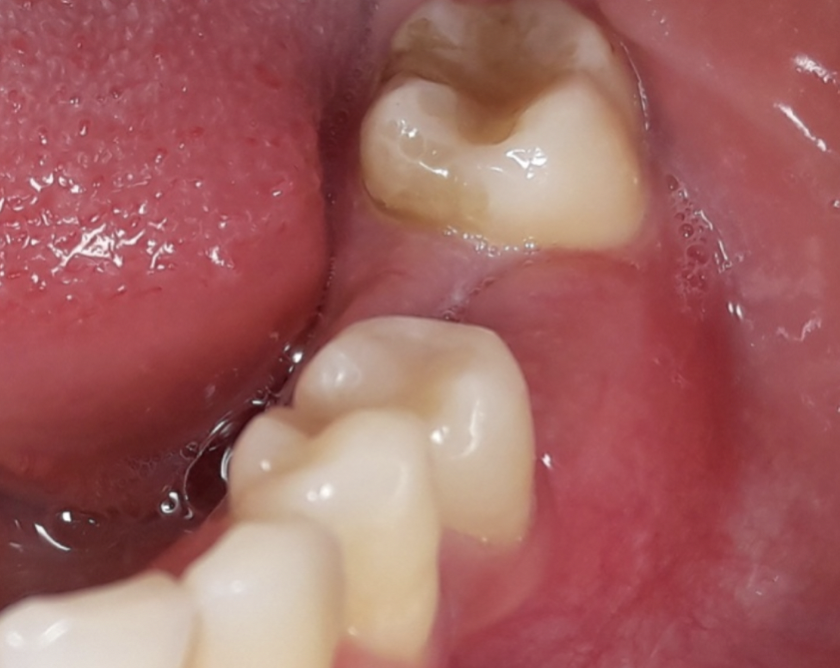

Nello studio sono stati inclusi 20 pazienti (12 donne e 8 uomini) di età compresa tra i 28 e i 65 anni, con edentulia singola e conseguente deficit vestibolare dei tessuti molli. La matrice dermica a elevata consistenza è stata opportunamente ritagliata mediante forbici e lama ed è stata posizionata al di sotto del lembo muco periostale allestito con approccio a spessore totale, vestibolarmente alla cresta ossea in cui è stato posizionato contestualmente un impianto endosseo osteointegrabile. Non si è utilizzato alcun ausilio di fissazione per la matrice dermica che è stata stabilizzata dal solo lembo di accesso ribaltato su di essa e suturato, mediante punti staccati semplici, al lembo linguale.

Le rilevazioni eseguite a distanza di 18 mesi di tempo medio, hanno mostrato un netto miglioramento del PES (Pink Esthetic Score) con un punteggio medio superiore a 9 (eccellente) e in due casi un punteggio tra 6 e 8 (buono). La sovrapposizione dei file .stl provenienti dalla scansione della arcata dentaria interessata prima dell’intervento e a distanza di 18 mesi ha permesso di rilevare un incremento medio in senso orizzontale di 2 mm in media.